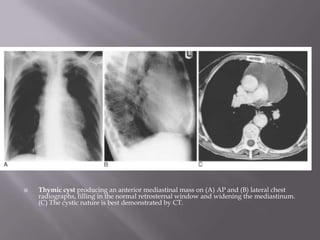

 Thymic cyst producing an anterior mediastinal mass on (A) AP and (B) lateral chest

radiographs, filling in the normal retrosternal window and widening the mediastinum.

(C) The cystic nature is best demonstrated by CT.